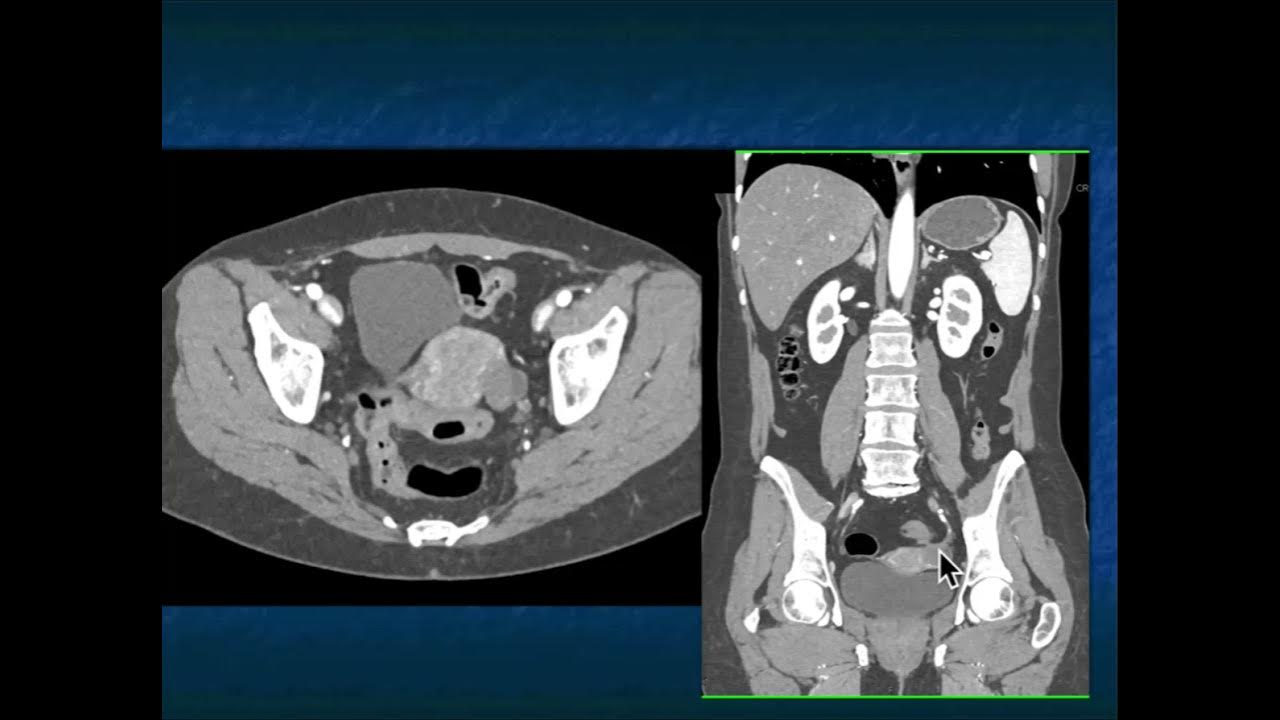

From www.youtube.com

CT Evaluation of Endometriosis YouTube Does Endometriosis Show Up In Ct Scan to find out if you have endometriosis, your doctor will likely start by giving you a physical exam. Density of small diameter sensory nerve fibres in endometrium: both imaging methods may show certain forms of endometriosis, such as advanced deeply infiltrating lesions or endometriomas (ovarian cysts). bokor a, kyama cm, vercruysse l, et al. the article. Does Endometriosis Show Up In Ct Scan.

From www.ctisus.com

Genitourinary Learning Modules CT Scanning Does Endometriosis Show Up In Ct Scan bokor a, kyama cm, vercruysse l, et al. both imaging methods may show certain forms of endometriosis, such as advanced deeply infiltrating lesions or endometriomas (ovarian cysts). based on clinical suspicion or findings at routine transvaginal pelvic us or other prior imaging, dedicated imaging for. Knowing the locations of possible endometriosis can aid your surgeon in planning. Does Endometriosis Show Up In Ct Scan.